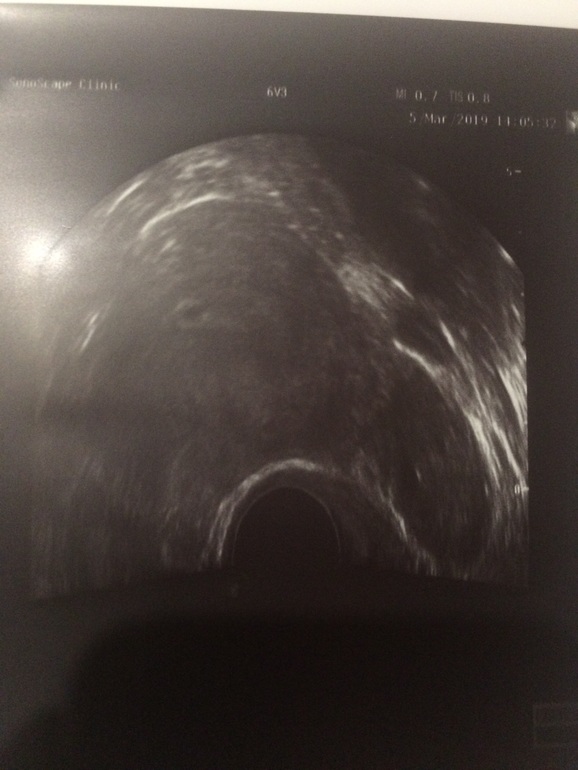

Узи после приема плодное яйцо 5 мм.срок от переноса на тот момент 4.6- так как прошло два дня получается уже 5.1 .малыш набирайся сил ,расти на радость маме папе и сестренки 🙏🏻